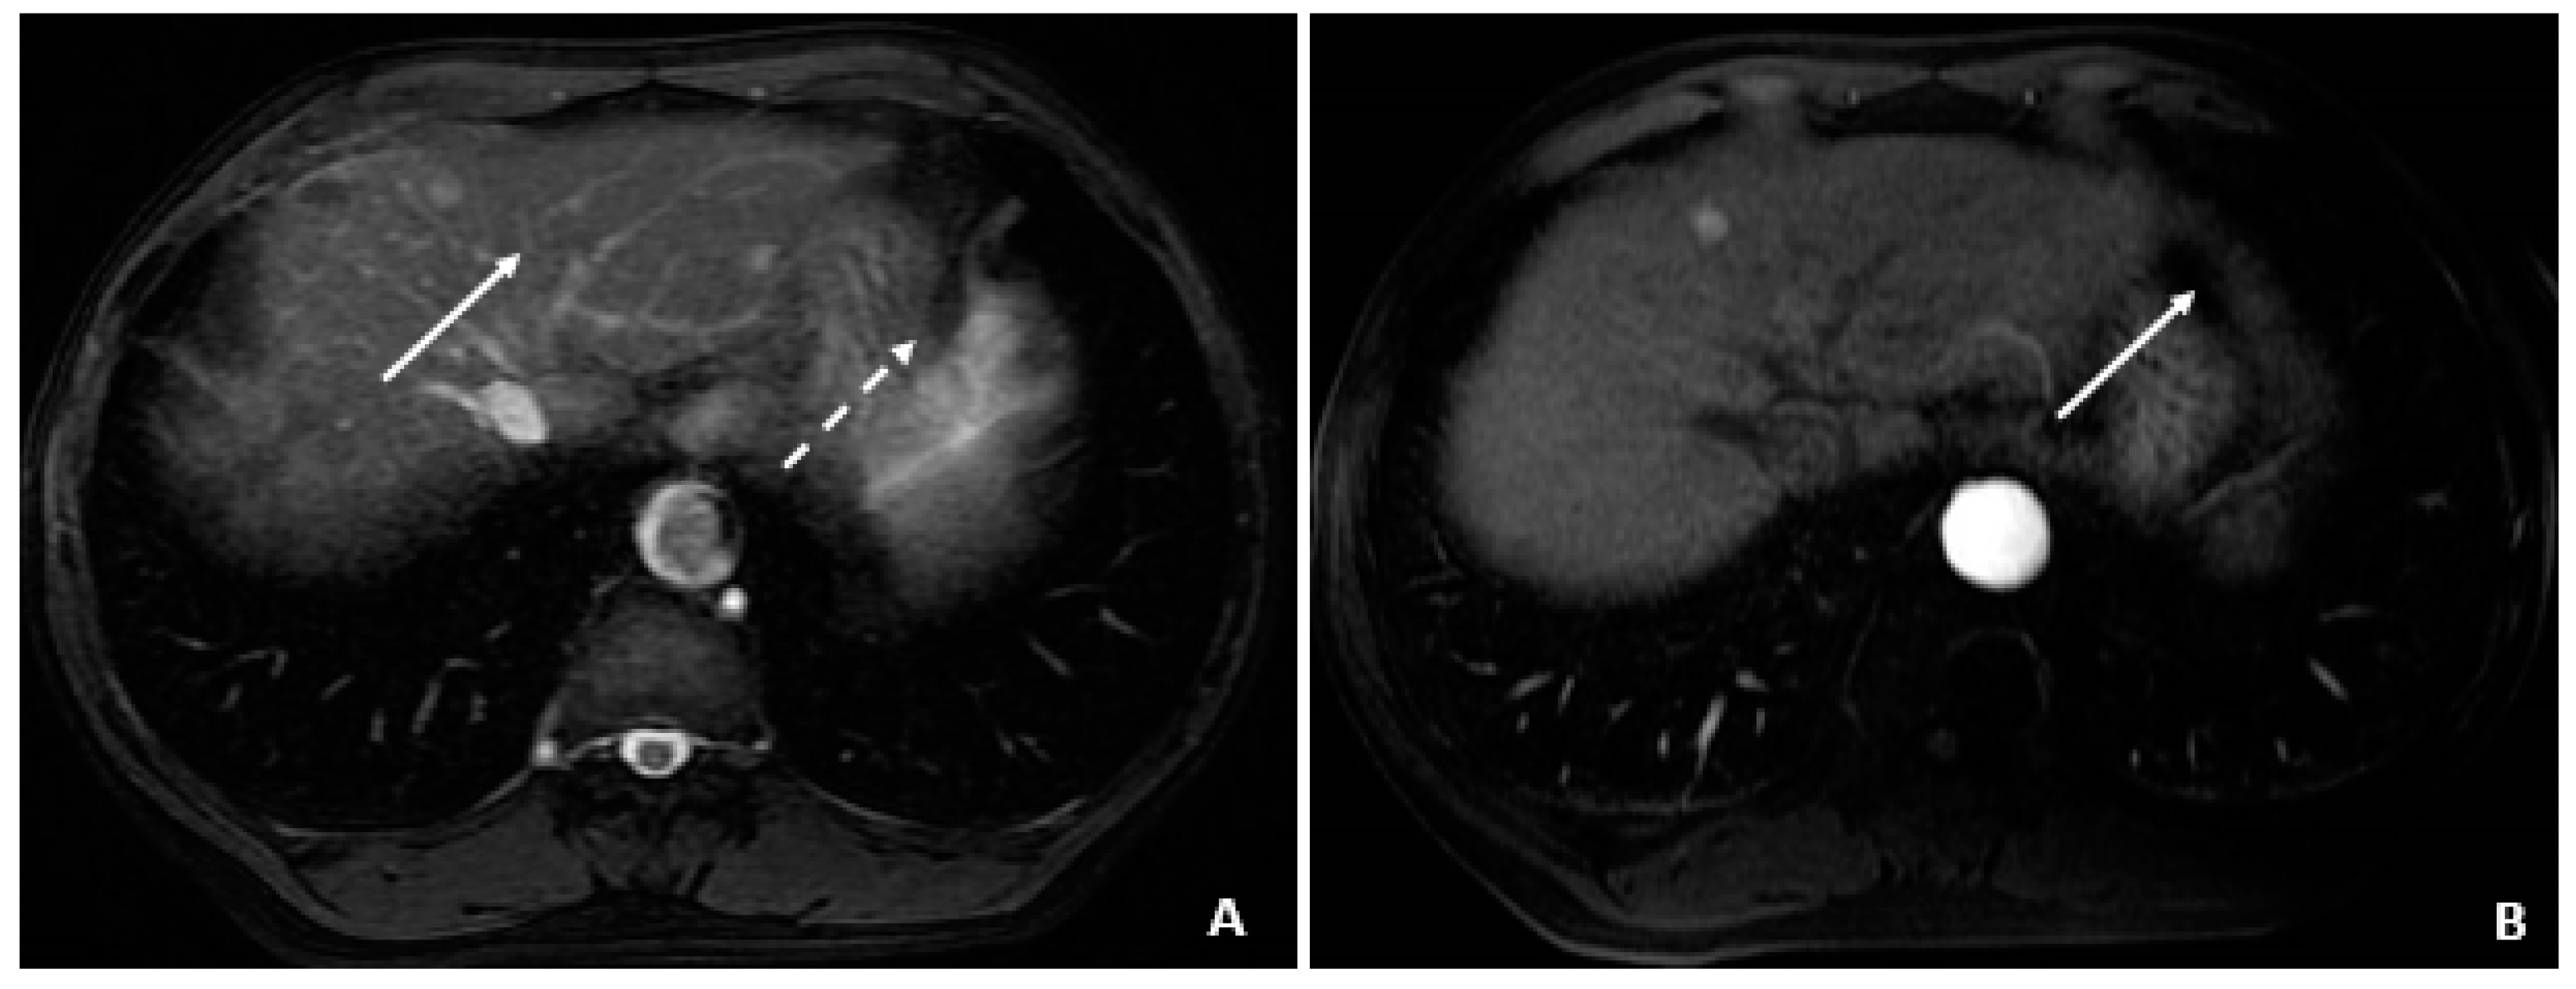

6.4. Case 4: A 50-Year-Old Male

A 50-year-old male was diagnosed with CHB at age 40. With lamivudine treatment for 3 years, he achieved HbsAg seroconversion to anti-HBs and lamivudine was discontinued. Table 4 outlines his course. Five years later, on a follow up examination he was found to have HBV DNA 847 copies/mL, ALT 33 IU/L, and AFP 20.5 ng/mL. An MRI (December 2009) showed a 5 cm lesion consistent with HCC (Figure 1A,B). Repeat AFP was 17.8 ng/mL at time of HCC diagnosis, and AFP-L3% was 75.6. He underwent transarterial chemoembolization (TACE) with successful resolution (Figure 2A,B) and restarted lamivudine. The AFP remained at 3.0 ng/mL, and the MRI showed no evidence of HCC the following year. Two years after initial treatment, the AFP increased to 5.9 ng/mL with 57.5% L3. The MRI next month showed recurrent HCC at the treated site (Figure 3). The patient underwent laparoscopic radiofrequency ablation and therasphere treatment.

Figure 2. Transarterial Chemoembolization (December 2009). (A) The selective left hepatic artery injection shows a blush of contrast corresponding to the hypervascular tumor (arrows). (B) An axial T1-weighted fat-suppressed portal-phase postcontrast MRI image 4 weeks following TACE shows lack of enhancement in the treated lesion with a small adjacent focus of necrosis (arrows).